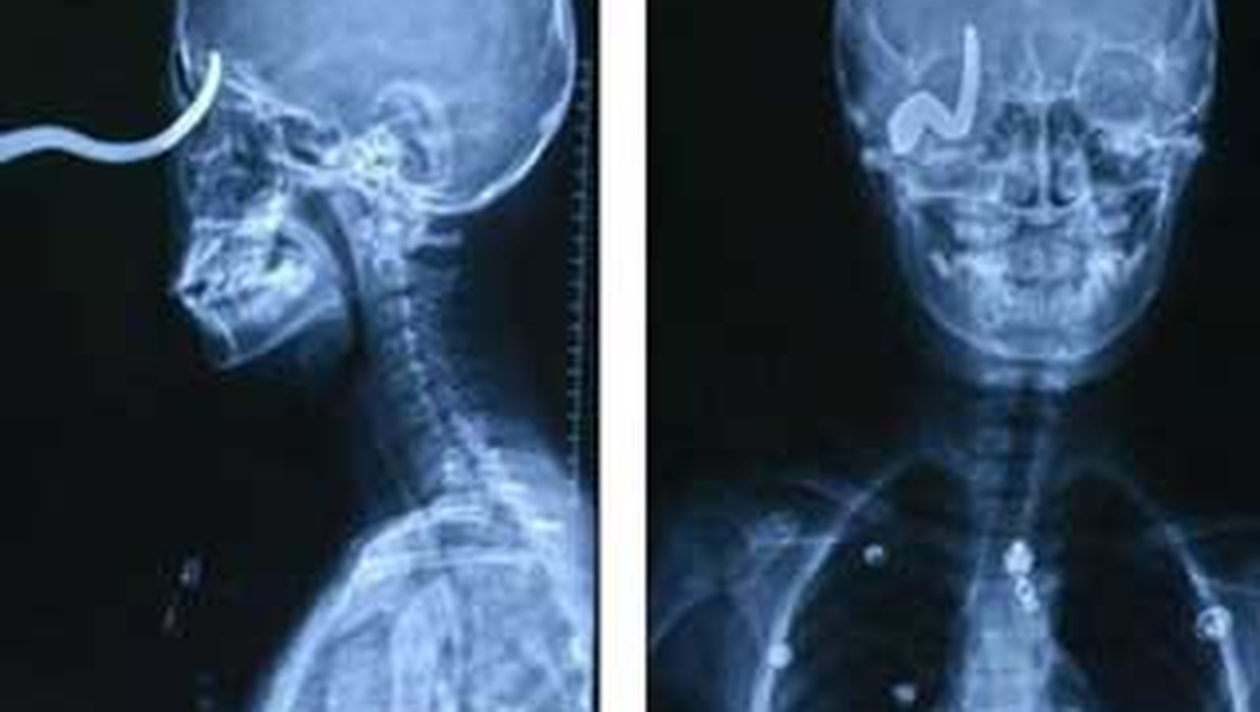

Un baiat de 13 ani din China a ajuns la spital cu un carlig infipt in craniu, care i-a trecut la doi milimetri de creier.

Din fericire adolescentul a scapat ca prin minune din ghearele mortii. Incidentul s-a petrecut in curtea scolii, in timp ce acesta se juca. Baiatul a alunecat, iar carligul i s-a infipt in cap.Acesta a fost dus de urgenta la spital si initial medicii au taiat partea carligului care a ramas in exterior pentru a-i face o radiografie.Baiatul a fost apoi operat si salvat de la moarte.